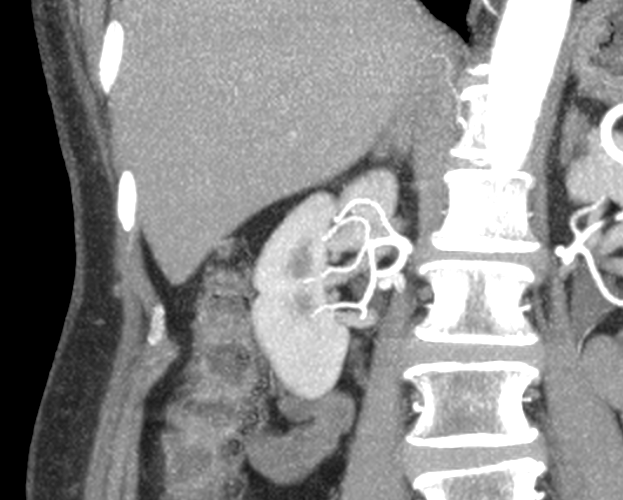

Una paciente de 74 años presenta un tumor de 22x25mm en su riñón derecho que fue hallado por un estudio de tomografía.

Luego de unos meses, la paciente vuelve al consultorio para realizar seguimiento, donde el doctor decide realizar una ecografía de control. En la misma, se reconfirma el diagnóstico de tumor renal hiliar en valva posterior del riñón derecho. Con este resultado, se decide realizar una intervención quirúrgica. Para la misma, dadas las características de la masa anómala, el Dr. Jurado solicita un modelo 3D para planificar la cirugía.

La planificación avanzada con biomodelos introdujo una gran mejora en la estrategia quirúrgica evitando situaciones inesperadas. Durante la intervención, el cirujano buscó identificar las estructuras importantes en la ubicación previsualizada en la impresión 3D, lo que permitió ir directo al tumor cuidando todas las estructuras anatómicas cercanas.

A la paciente se le realizó una nefrectomía parcial lumboscópica derecha por vía retroperitoneal. El procedimiento completo duró 65 min. y el tiempo de isquemia fue de 20 min.